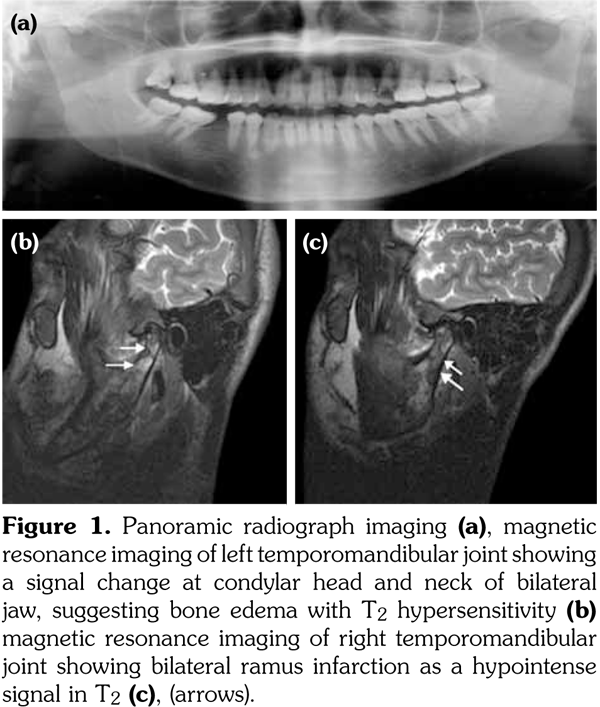

A 24-year-old male patient was admitted to the Otorhinolaryngology Department with complaints of pain for three days in the bilateral preauricular region. The pain was constant, severe, and increased when he reclined, chewed or talked. There was no medical history of fever or trauma. Physical examination findings included mild edema, allodynia, and hyperalgesia in the bilateral preauricular area and bilateral masseter muscle. Panoramic radiograph showed limited interincisal mouth opening (12 mm) (Figure 1a). A written informed consent was obtained from the patient.

Initial laboratory tests showed serum C-reactive protein of 154 mg/L (0-5), ferritin of 1314 ng/mL (15-200), leukocyte count of 22.1x103/μL (4-10), hemoglobin of 10.1 g/dL (10-17), and total bilirubin of 2.31 mg/dL (0-1.1). The test for rheumatoid factor was negative. Significant inflammatory processes were seen on magnetic resonance imaging in T2 (Figure 1b) and necrotic areas in the right ramus of the mandible were also seen as a hypointense signal in T2 (Figure 1c). Arthritis in the bilateral condylar head secondary to a sickle cell crisis was diagnosed after the analysis of the laboratory tests and images.